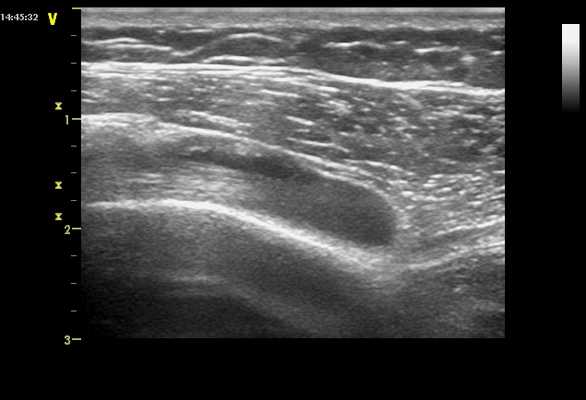

Подвывих сухожилия длинной головки бицепса при ультразвуковом исследовании

Длинную головку сухожилия бицепса (СДГБ) можно оценить, когда пациент находится в нейтральном положении, его локоть согнут, а тыльная сторона кисти находится на ипсилатеральном бедре. СДГБ видена как «шнуроподобная» гиперэхогенная структура, которая лежит внутри биципитальной борозды между большим и малым бугорком проксимального отдела плечевой кости и покрыта поперечной плечевой связкой. В нормальном плечевом суставе СДГБ закрепляется сухожильной оболочкой и биципитальной бороздой, а также поперечной плечевой связкой, так что оно не подвисает и не вывихивается при внутреннем или внешнем вращении плеча.

Динамическая оценка подвывиха или вывиха СДГБ была впервые введена на УЗИ в 1995. Во время исследования было обнаружено, что максимальное внешнее вращение плеча было полезно для диагностики преходящего подвывиха сухожилия бицепса, и чувствительность динамической оценки составила 86%. Также было предложено, чтобы динамическое исследование для подвывиха СДГБ должно включаться в рутинные исследования плечевого сустава. Подвывих и вывих сухожилия бицепса часто сообщается с неглубокой биципитальной бороздой и разрывом ротаторной манжеты, особенно при разрыве сухожилия подлопаточной мышцы. Биципитальная борозда глубиной менее 3 мм на УЗИ считается неглубокой. Диагноз подвывиха или вывиха может быть поставлен, когда СДГБ выходит за стенку своей канавки или выходит из нее при осмотре по короткой оси, когда рука находиться в нейтральном, либо в положении внешнего вращения.